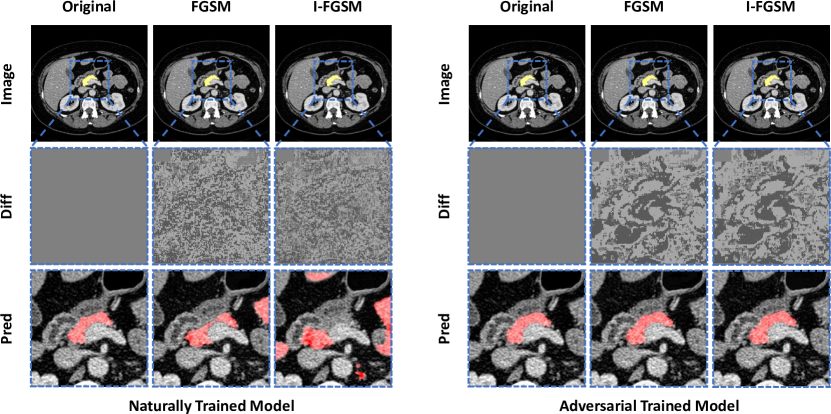

Robustness Evaluation

To evaluate the robustness of our well-trained 3D model, we attack the ResDSN Coarse model following the methods in Sec. 3.2. For both attacking methods, i.e., FGSM and I-FGSM, we set so that the maximum perturbation can be small enough compared with the range of the truncated intensity value ()††Since the raw intensity values are to be in during preprocessing (see Sec. 4.1), here we set accordingly.. Specially in the case of I-FGSM, the total iteration number and the step size are set to be and , respectively. Following the test strategy in the coarse stage, we first compute the loss gradients of the sub-volumes††For implementation simplicity and efficiency, we ignored the sub-volumes only containing the background class when generating adversarial examples. obtained by a sliding window policy, and these gradients are then combined to calculate the final loss gradient map of each whole CT volume. The combine approach is also similar as the testing method described in Sec. 4.1, i.e., taking the average of loss gradient if a voxel is in the overlapped region. According to Eq. 6 and Eq. 7, the overall loss gradient can be used to generate adversarial examples which can then attack the 3D model for the purpose of robustness evaluation.

Results and Discussion

All attack and defense results are summarized in Table 8. We can see that both attack methods, i.e. FGSM and I-FGSM, can successfully fool the well-trained 3D ResDSN into producing incorrect prediction maps. More specifically, the dramatic performance drop of I-FGSM, i.e., (from to ), suggests low adversarial robustness of the original model. Meanwhile the maximum performance drop decreases from to , indicating that our adversarially-trained model can largely alleviate the adversarial effect and hence improving the robustness of our 3D model. Note that our baseline with “Clean” training has accuracy when tested on clean images, whereas its counterpart with adversarial training obtains . This tradeoff between adversarial and clean training has been previously observed in tsipras2018robustness . We hope this tradeoff can be better studied in future research.

We also show a qualitative example in Fig. 5. As can be observed from the illustration, adversarial attacks to naturally trained 3D ResDSN induces many false positives, which makes the corresponding outcomes noisy. On the contrary, the adversarially trained 3D model yields similar performances even after applying I-FGSM. More specifically, the original average Dice score of 3D ResDSN is , and after applying adversarial attack the performance drops to and with FGSM and I-FGSM respectively. However, when applying the same attack methods to the adversarial trained model, the performance only drops from to and respectively. In other words, employing adversarial training decreases the performance drop from to only . This promising result clearly indicates that our adverarially-trained model can largely improve the adversarial robustness.